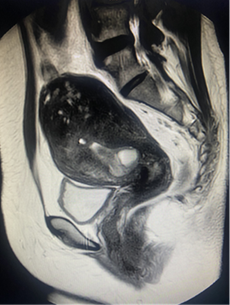

盆腔MR:

1.子宫腺肌病(宫体约9.8cm*7.0cm,结合带不均性增厚,约3.2cm,与肌层分界模糊,肌层信号欠均,最大位于左下壁,直径约2.5cm)

2.子宫内膜息肉(2.3cm*1.1cm*1.1cm)